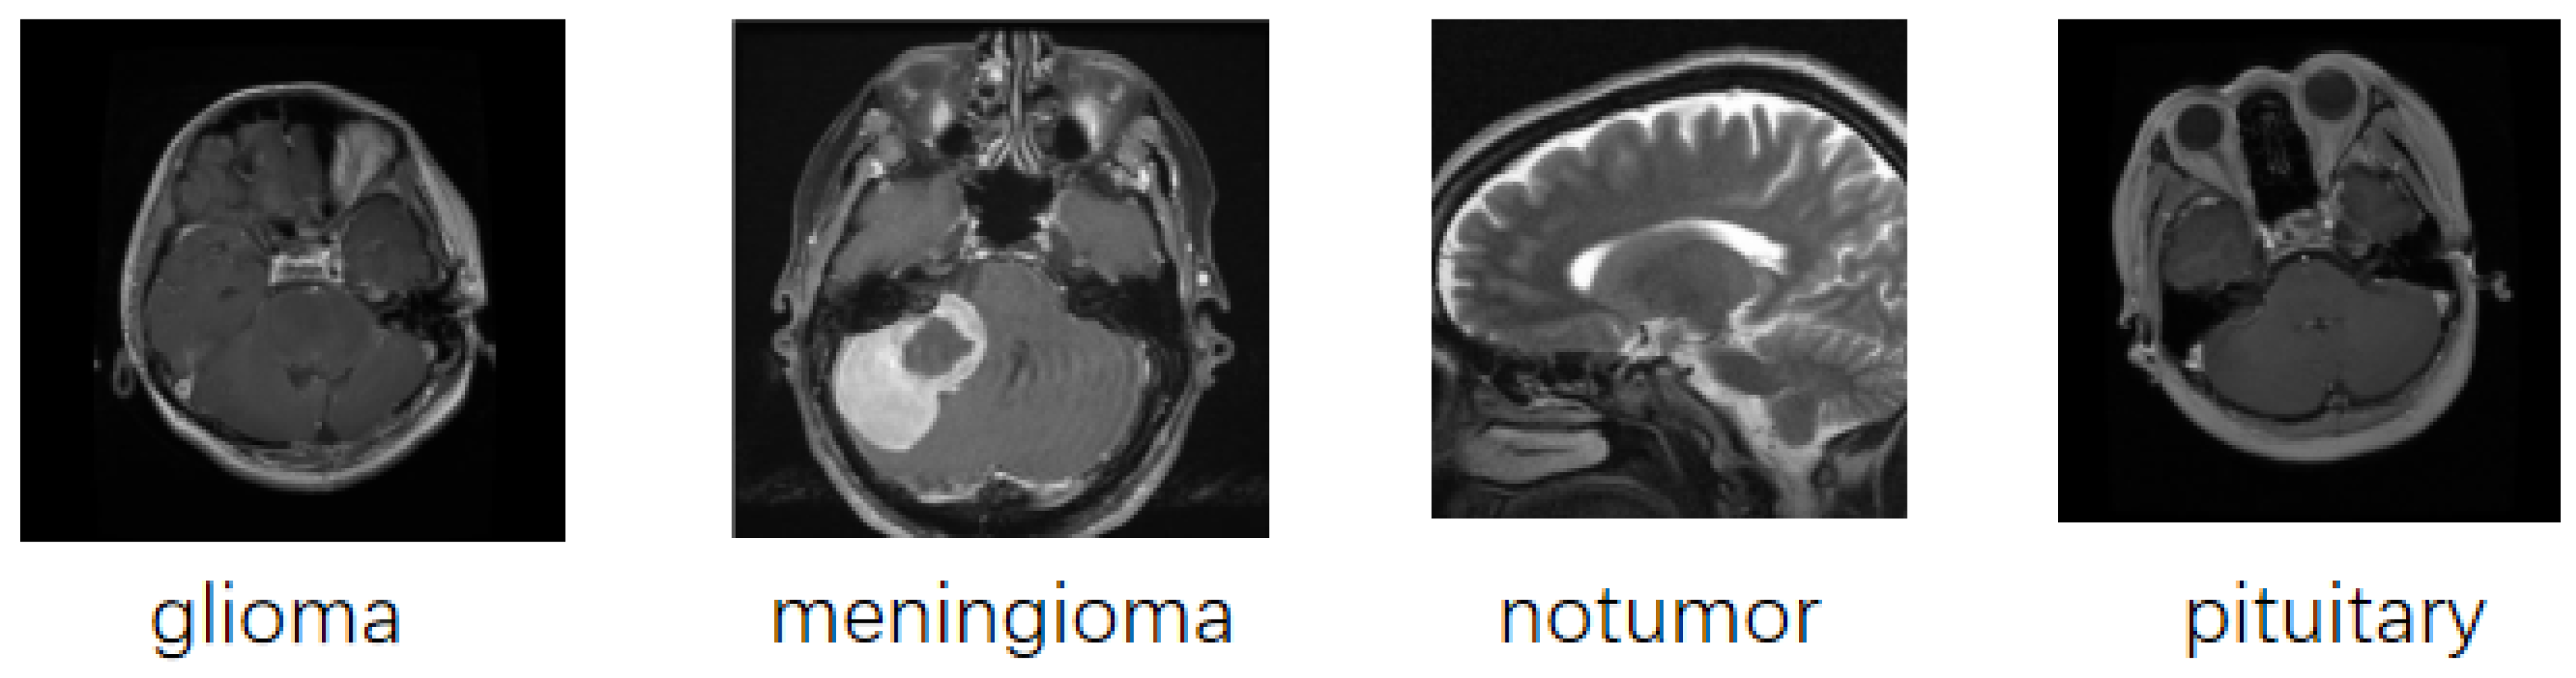

2.1. Dataset

- Nickparvar, M. Brain tumor MRI dataset. Kaggle 2021. [Google Scholar]